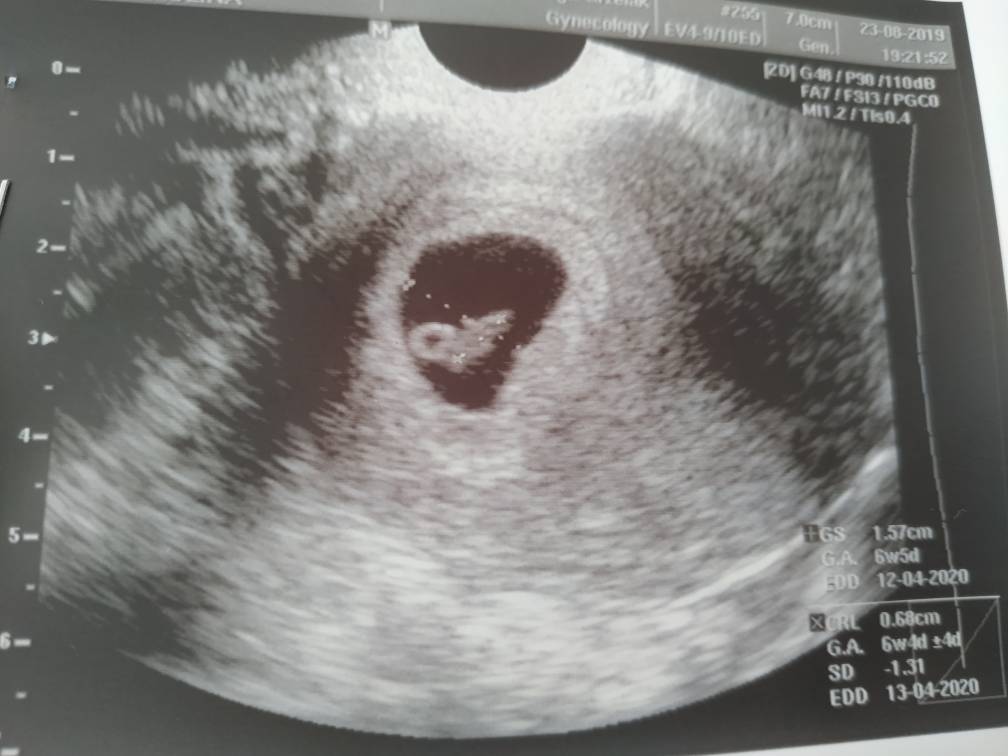

No to ja zacznę pierwsza. Wszystko ok! [emoji3526] Jest akcja serca, zero śladów jakichkolwiek krwawień. Niepotrzebna panika.

IMG_20190823_121236.jpeg